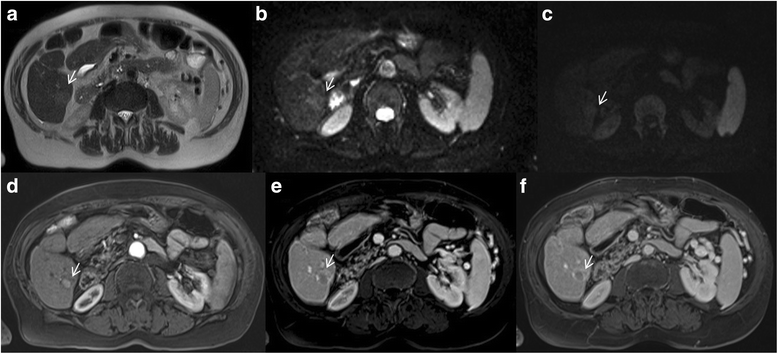

Man 73 years old with typical HCC on VI hepatic segment. The HCC is hyperintense (arrow) on T2-W sequences (a), shows (arrows) restrict diffusion (b: b50 s/mm2, c: b800 s/mm2). After contrast medium injection, the nodule is hypervascular (arrow) on arterial phase (d), with wash-out appearance (arrow) on portal phase (e) and capsule appearance (arrow) on equilibrium phase (f) of contrast study with Gd-BT-DO3A